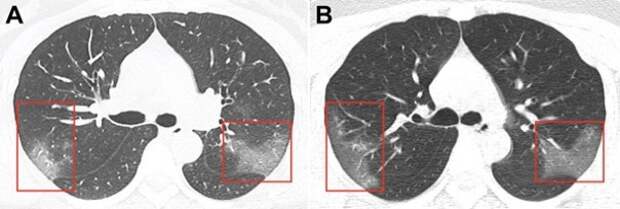

Опубликованы снимки пораженных коронавирусом легких

Китайские медики опубликовали фотографии легких пациентки, которая заразилась коронавирусом 2019-nСоV. Изображения, опубликованные в журнале Radiology 31 января.

Снимки были получены в результате компьютерной томографии 33-летней женщины, госпитализированной в китайском городе Ланьчжоу с температурой 39 градусов.

Снимки были сделаны с разницей в три дня. На первом из них в низу легких уже заметны зоны поражения инфекцией — они похожи на большие светлые области. На снимке, сделанном спустя три дня уже заметно, что зона поражения расширяется.